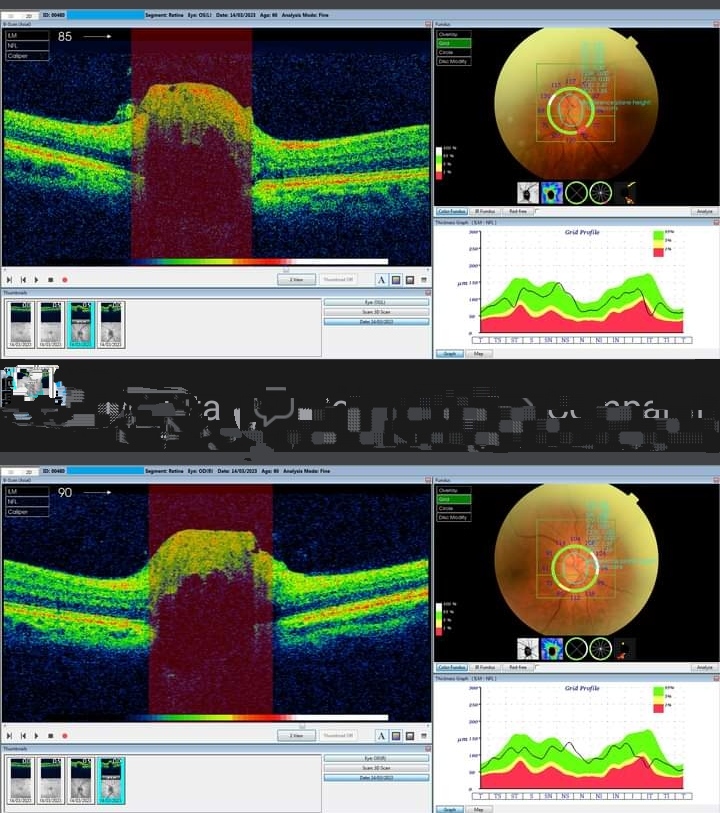

LLas drusas en el nervio óptico son conjuntos de calcio y otras proteínas que se acumulan en esta zona del ojo y que tienen forma redondeada.

Suelen aparecer a partir de los 10 años y se mantienen en el ojo, sin causar síntomas, durante varios años. Asimismo, generalmente, se manifiestan durante la vida adulta, momento en el que crecen y provocan una pérdida progresiva y degenerativa de la visión periférica.

Los primeros síntomas de las drusas en el nervio óptico suelen aparecer a partir de los 30 años.